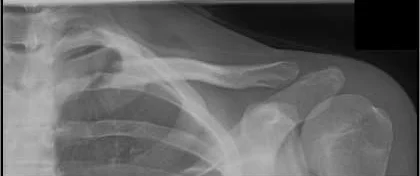

- Sites:

- Lateral thirds,

- Middle thirds, common (why?)

- Medial thirds

Its weakest point. The lateral fragment is depressed by the weight of the arm against trapezius, thus the shoulder droops, it is pulled medially forward by adductor function of pectoralis major causing the bone fragments to override.